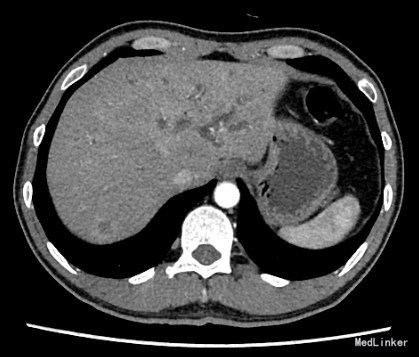

查体:身目重度黄染,上腹部轻压痛; 辅助检查: 白细胞WBC:10.96; 血红蛋白Hb:145g/L;血小板PLT:241x10^9/L 丙氨酸氨基转移酶ALT 357 U/L ;天冬氨酸氨基转移酶AST 191 U/L;白蛋白ALB 40.9 g/L ;总胆红素TBIL 151.2 umol/L;直接胆红素DBIL 85.8 umol/L 肿瘤标记物: 甲胎蛋白(AFP) 5.00 ug/L 0.00 - 20.00 ;癌胚抗原(CEA) 9.19 ug/L ↑ 0.00 - 5.00 ;CA125 71.00 U/mL ↑ 0.00 - 35.00 鳞癌抗原(SCC) 0.90 ug/L 0.00 - 1.50 ;CA19-9 〉12000.00 U/mL CT:平扫胰体尾部萎缩,胰头区不规则肿大,局部可见类圆形软组织肿块影,大小约44×43mm,边界模糊,内部密度不均,其内可见斑点状钙化灶,并见更低密度区。增强扫描正常胰腺组织明显强化而肿物轻度强化,显示较清楚;强化不均匀,中央有低密度坏死区。肿块与十二直肠降段分界不清,病变包绕肠系膜上静脉,血管见充盈缺损影,胰头周围及腹膜后见肿大的淋巴结影。、、、 1.胰头癌,侵犯十二指肠降段及肠系膜上静脉,胰周及腹膜后多发淋巴结轻度肿大。 2.肝S7病灶,高度怀疑转移瘤。 超声造影提:胰头病变:考虑胰头Ca。 肝S7病变:考虑MLC。 肝内外胆管弥漫性扩张。胆囊壁增厚。腹膜后淋巴结肿大。脾脏超声检查未见异常。